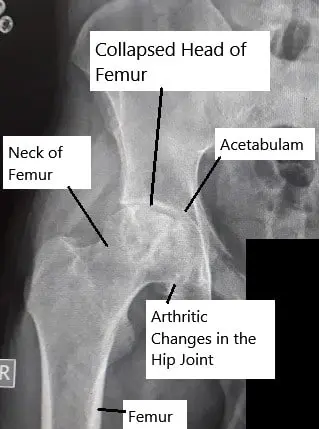

The hip joint is a ball-and-socket joint formed by the femoral head (ball) and the acetabulum (socket). The femoral head receives its blood supply through small arteries that run along the neck of the femur. When these arteries are disrupted or compressed, the blood flow stops, leading to bone death in the femoral head. Over time, the joint loses its round shape, causing pain and stiffness.

X-ray showing avascular necrosis of the hip joint.